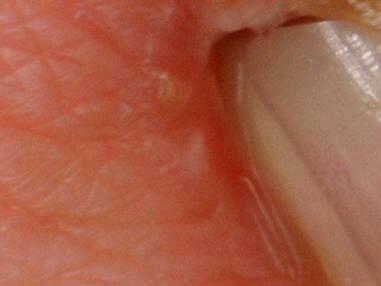

出口部周囲のドライスキン 61 歳、女性、心タンポナーデ

スキンケアせず洗浄した症例の導入3週目。

洗浄で保湿成分を失い雲母状に角質層が剥離しています。

肌理は左下から右上に流れています。

炎症反応がおきているために皮下の水分量が多く、写真では皮丘が拡張し盛り上がっています。